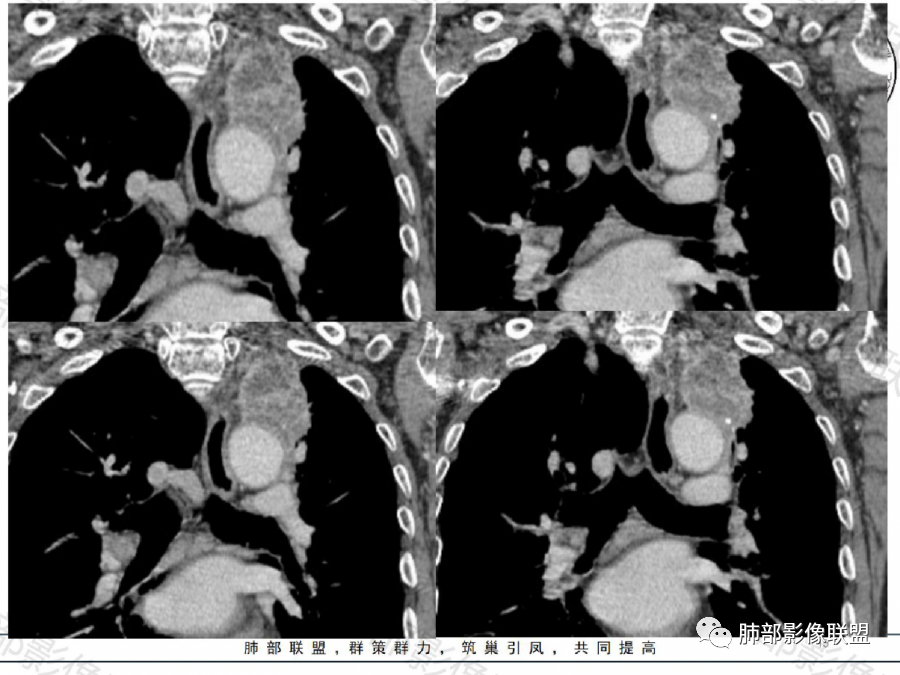

影像表现特点:左肺上叶纵隔旁主动脉弓上方实性肿块影,不规则,膨胀性生长,有棘状突起及收缩,肿块内密度不甚均匀,隐约见小钙化灶。周围具有一定的分叶及长短不一的毛刺征象,外围有小斑片影。矢状位显示支气管截断。增强扫描病灶不均匀强化,内部见小片状的坏死,呈典型的“沼泽样”改变。总体分析恶性征象更多。支持肺癌-鳞癌,支气管截断具有强烈提示意义。